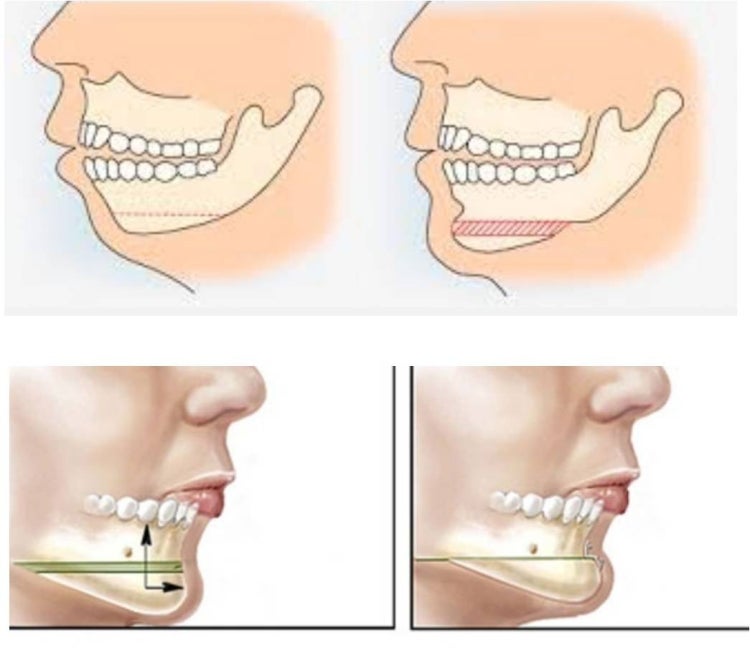

1. 턱끝 전진술

돌출 입이 없으며 순수하게 무턱 일 경우 이면서 턱끝의 길이가 길지 않은 소위 말하는 " 짧은 무턱"의 경우에 해당됩니다.

무턱이 심해서 4mm이상 전전이 필요할 경우에 시술 하며,

입안으로 절개를 하기에 밖으로 보이는 흉은 전혀 없습니다.

절골후에 필요한 만큼의 전진 mm 수를 정확히 측정하여 앞으로 당겨서 고정을 하는 방법입니다.

2. 이중 턱끝 축소 전진술(일명 샌드위치 절골술)

턱끝을 이중으로 절골하여 “자가뼈”로 무턱 수술을 하는 방법 방법입니다:

돌출입을 동반 하거나 동반 하지 않은 얼굴이 각진 얼굴 또는 무턱이 심한 경우 적합하며, 턱 끝을 수평으로 이중으로 절골하여 앞으로 당긴 상태에서 고정해 주는 수술입니다.

수술은 전신 마취하에서 수술을 하며 수술시간은 20-30 분이면 끝납니다